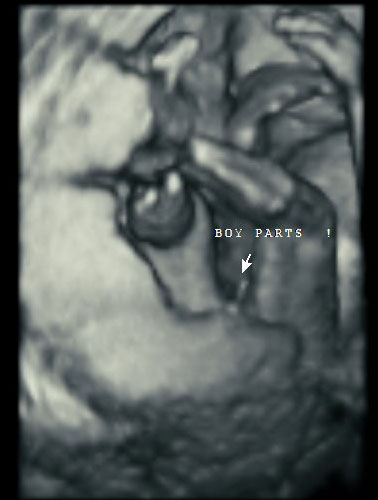

Here’s how ultrasound works in pregnancy: As early as 16 weeks, women can see a “fetal portrait” of their baby and determine its gender. Ultrasound technology has improved dramatically over the decades from flat, grainy black and white images to the current three-dimensional time experience.

How far along do you have to be for a gender scan?

Gender can usually be determined at 16 weeks.